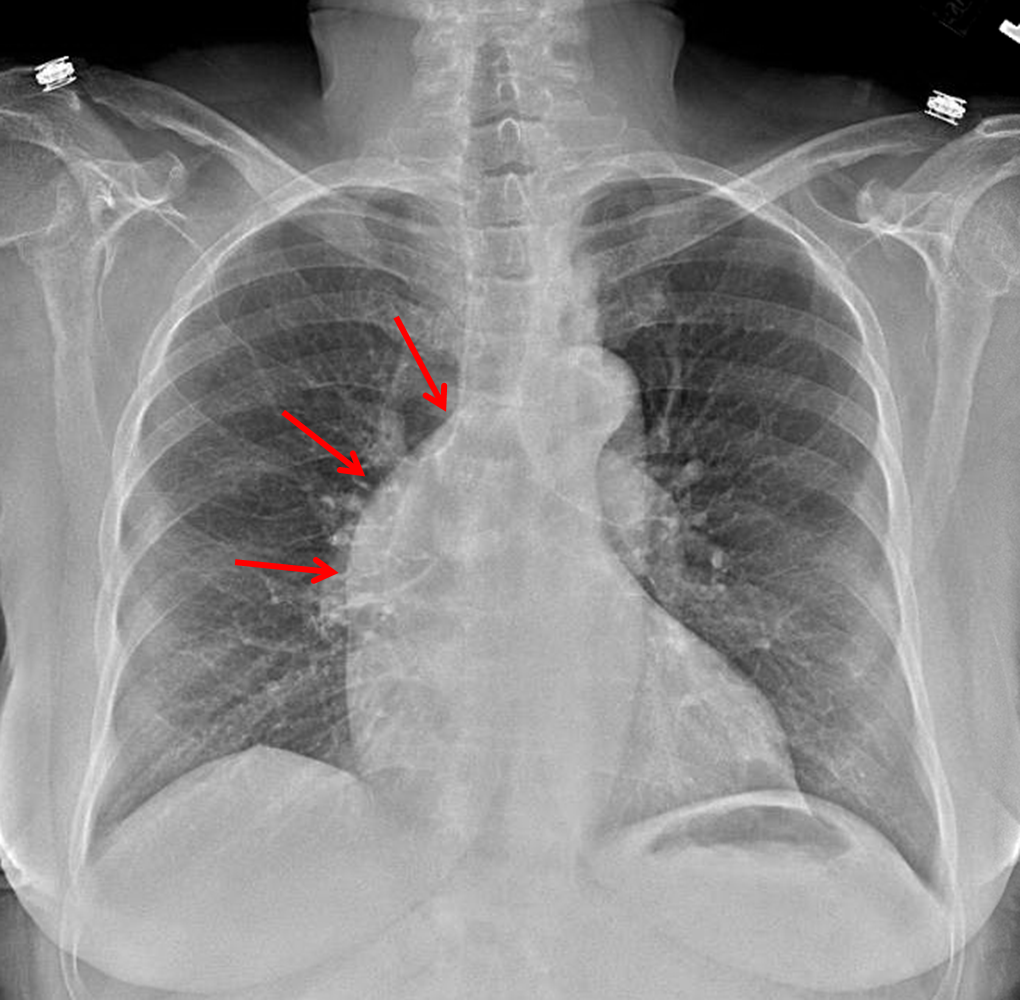

Age: 77

Sex: Female

Indication: Fever

Sample ReportAscending aortic aneurysm. Recommend chest CTA for further evaluation.

Otherwise, no evidence of acute cardiopulmonary disease.